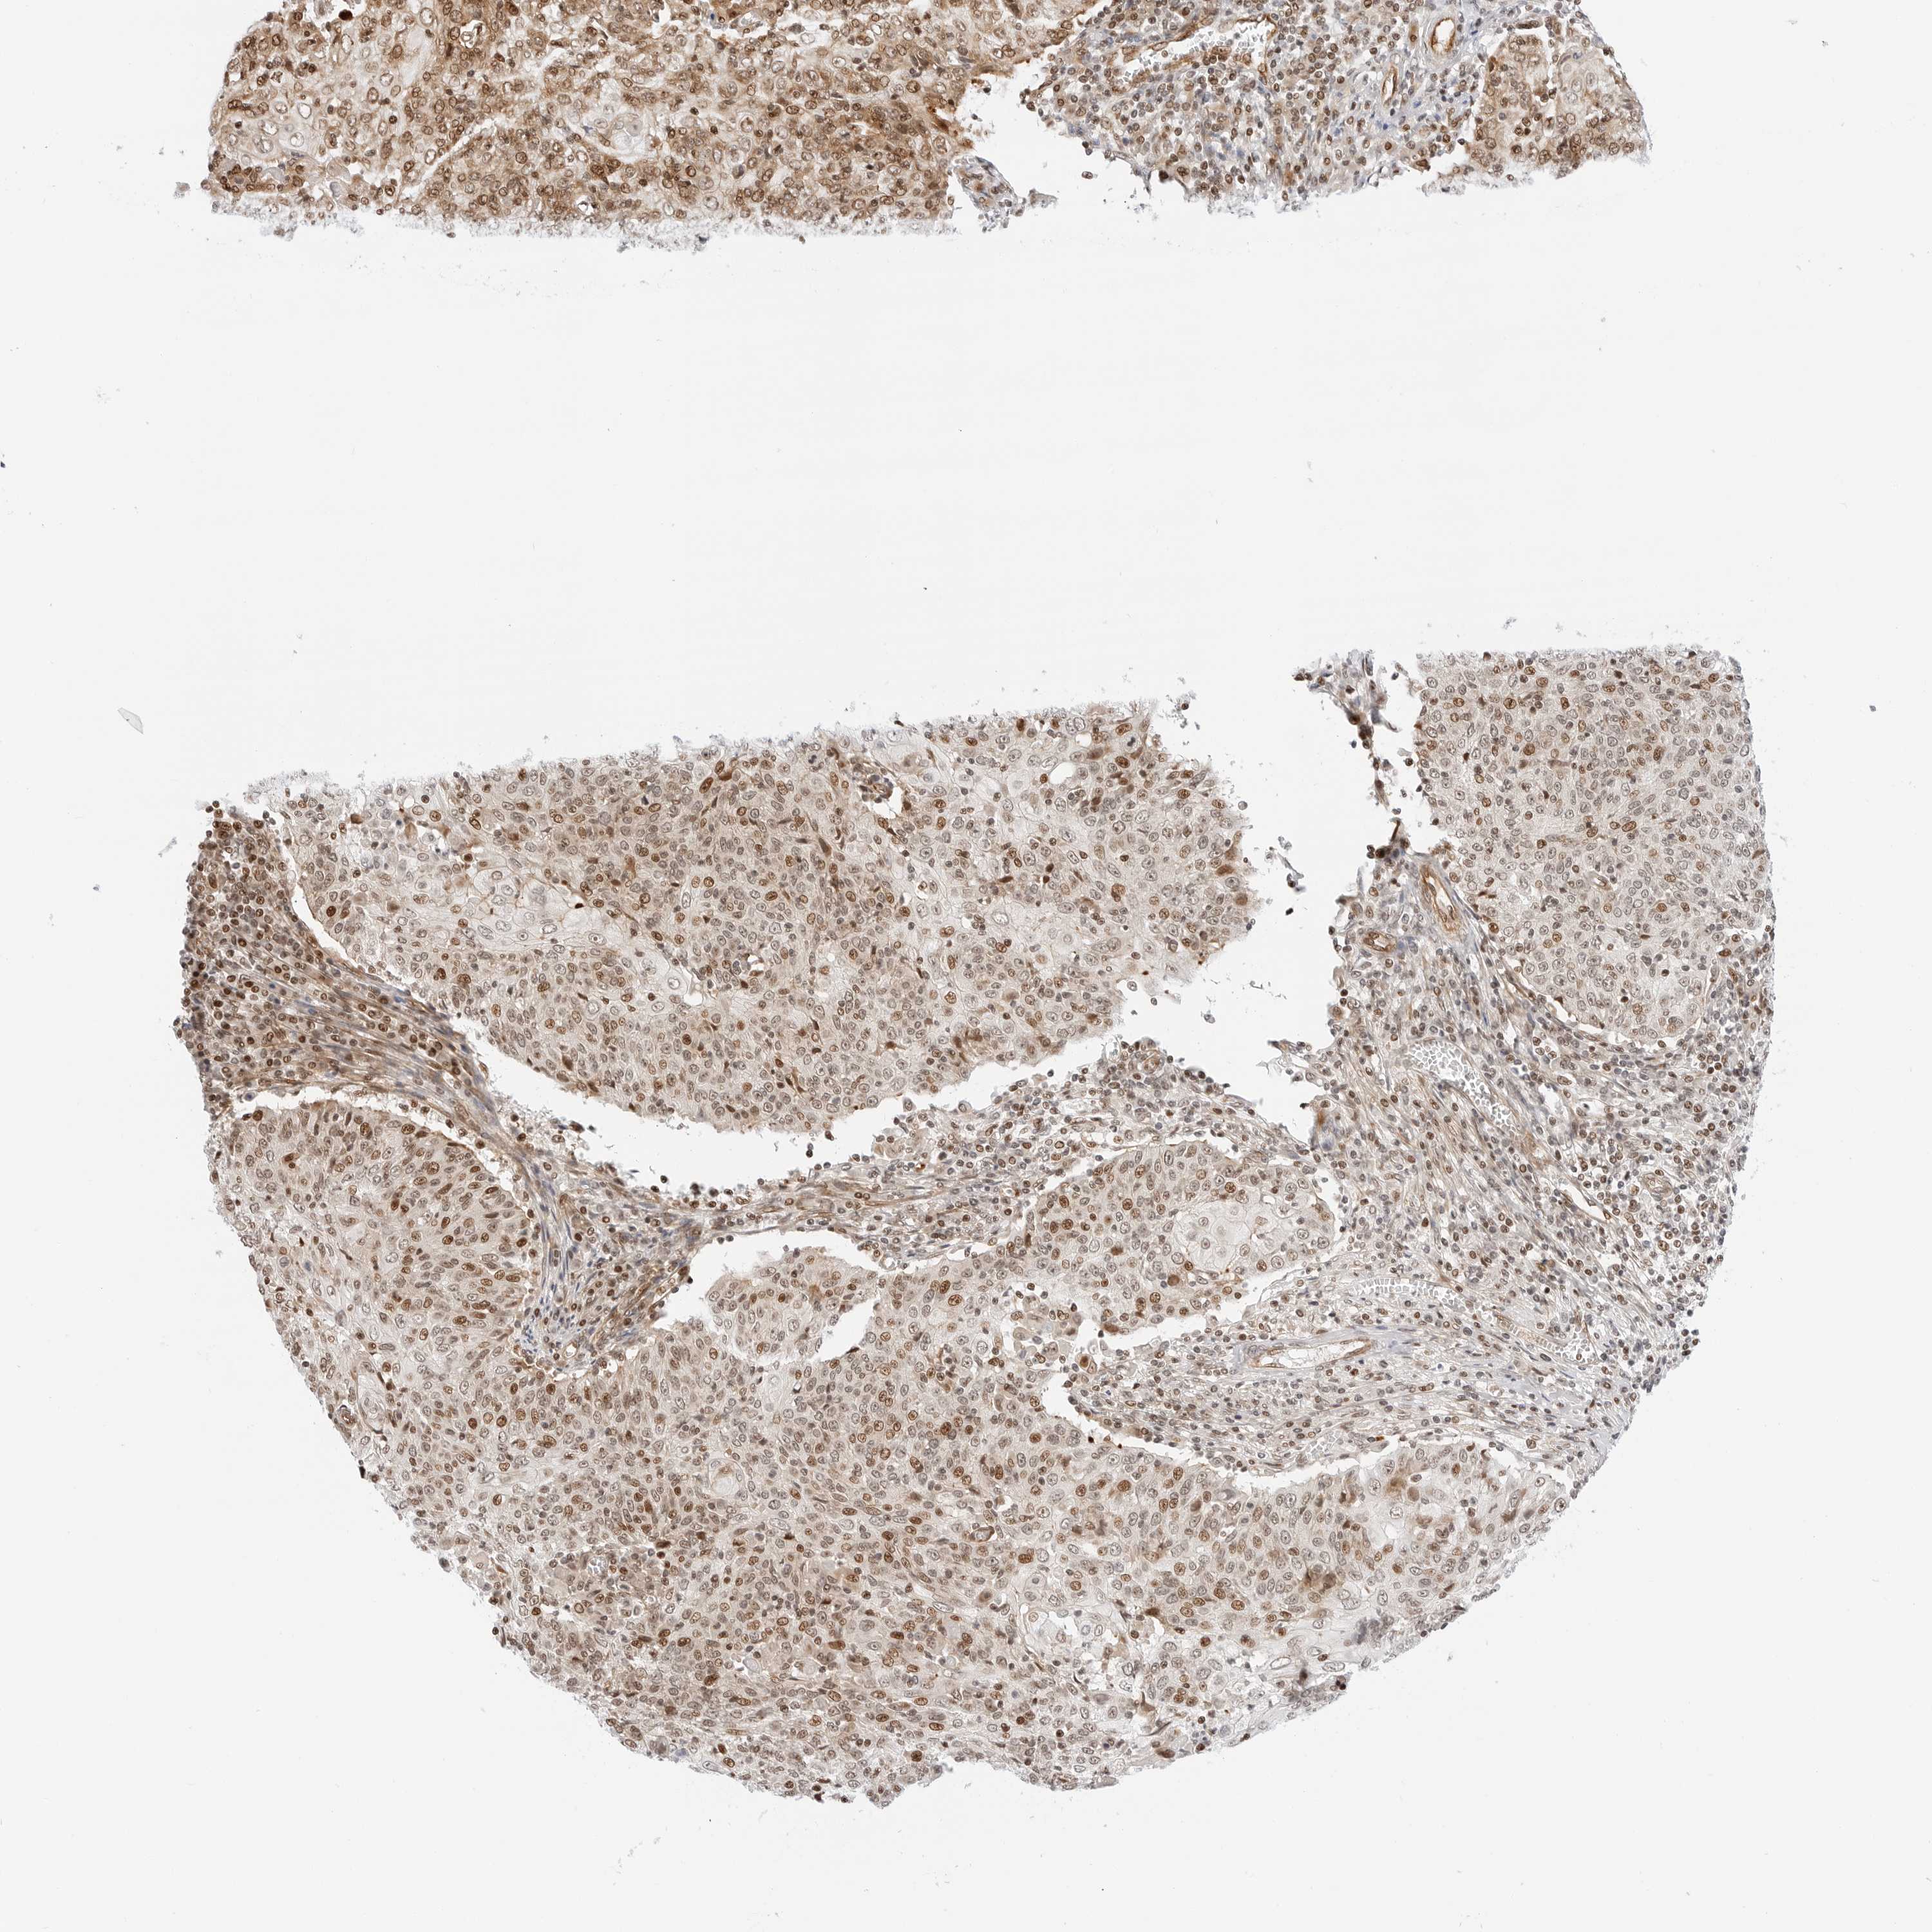

CERVICAL CANCER - Protein expressioni

A mouse-over function shows sample information and annotation data. Click on an image to view it in a full screen mode. Samples can be filtered based on level of antibody staining by selecting one or several of the following categories: high, medium, low and not detected. The assay and annotation is described here.

Note that samples used for immunohistochemistry by the Human Protein Atlas do not correspond to samples in the TCGA dataset.

Antibody stainingi

Antibody staining in the annotated cell types in the current human tissue is reported as not detected, low, medium, or high, based on conventional immunohistochemistry profiling in selected tissues. This score is based on the combination of the staining intensity and fraction of stained cells.

Each image is clickable and will lead to virtual microscopy that enables deeper exploration of all samples and also displays staining intensity scores, fraction scores and subcellular localization as well as patient and tissue information for each sample.

Antibody HPA026833

Staining

High

Medium

Low

Not detected

Intensity

Strong

Moderate

Weak

Negative

Quantity

>75%

75%-25%

<25%

None

Location

Nuclear

Cytoplasmic/membranous

Cytoplasmic/membranous,nuclear

Squamous cell carcinoma, NOS

Adenocarcinoma, NOS